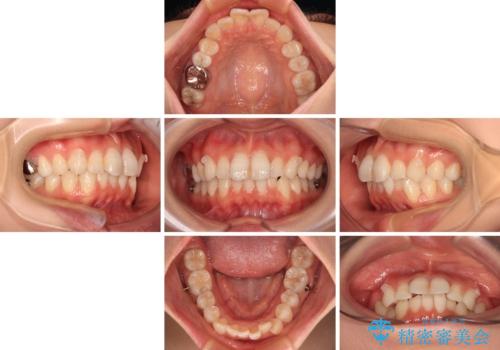

- 上下前歯のデコボコを改善したいとのことで来院された患者様です。

マウスピースを長時間装着し続ける自信はあまりないとのことでしたが、目立たない装置であれば頑張って装着するとのことで、インビザラインによる矯正治療を行うこととしました。

初めの1年くらいは何とか頑張って装着してくださいましたが、途中から変化をあまり感じられなくなり、日々の装着時間は徐々に短くなってしまいました。

前歯のデコボコはもっと改善できましたが、3年半が経過し、初診時と比べたら大幅に良くなったとのことで終了することとなりました。